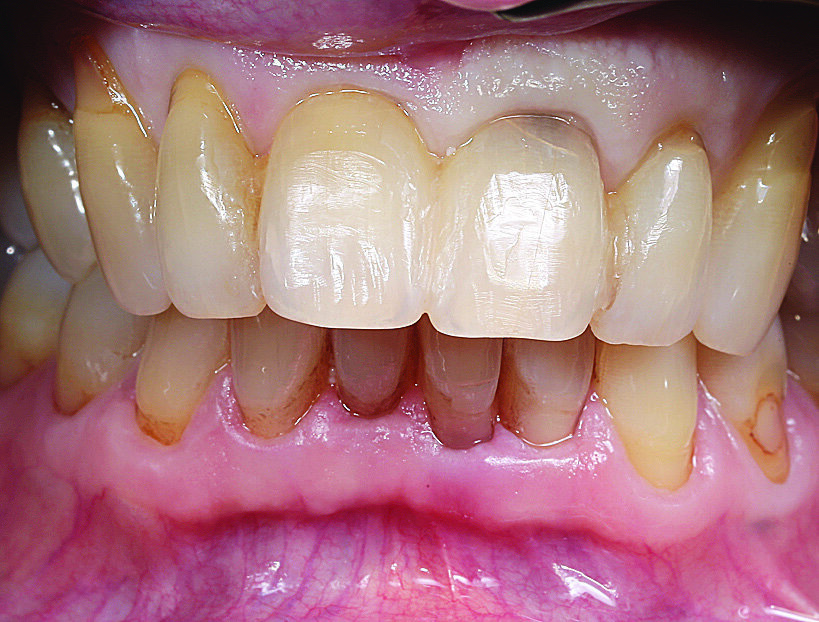

Budući da se to nije moglo isključiti za zub 21, u narednim posjetima provedeno je endodontsko liječenje s naknadnim punjenjem korijenskog kanala s MTA-om do pukotine (Slika 3.). Budući da je pacijent izrazio želju da se ne narušava estetika, za splintiranje je upotrijebljena palatinalna udlaga od PMMA-e (Slika 4.). Nakon tri mjeseca uočena je sve veća promjena boje zuba 21 i perzistentna pomičnost II. stupnja (Slika 5.). Nakon detaljnog informiranja o raznim mogućnostima liječenja kliničar i pacijent donijeli su odluku o implantoprotetskoj terapiji. CBCT snimljen tijekom planiranja terapije (Slika 6.), pokazao je blizak odnos prema vestibularnoj koštanoj lameli (položaj korijena I. razreda)14. Da bi se stvorio stabilan profil mekog i tvrdog tkiva i pacijentu što prije osigurao dobar estetski rezultat, kliničar se odlučio na imedijatnu implantaciju uz primjenu socket shield tehnike.

Slika 1. Početna situacija: Frontalni prikaz reponiranih i splintiranih zubi 11 i 21

Slika 5. Stanje nakon tri mjeseca: promjena boje na zubu 21 cervikalno